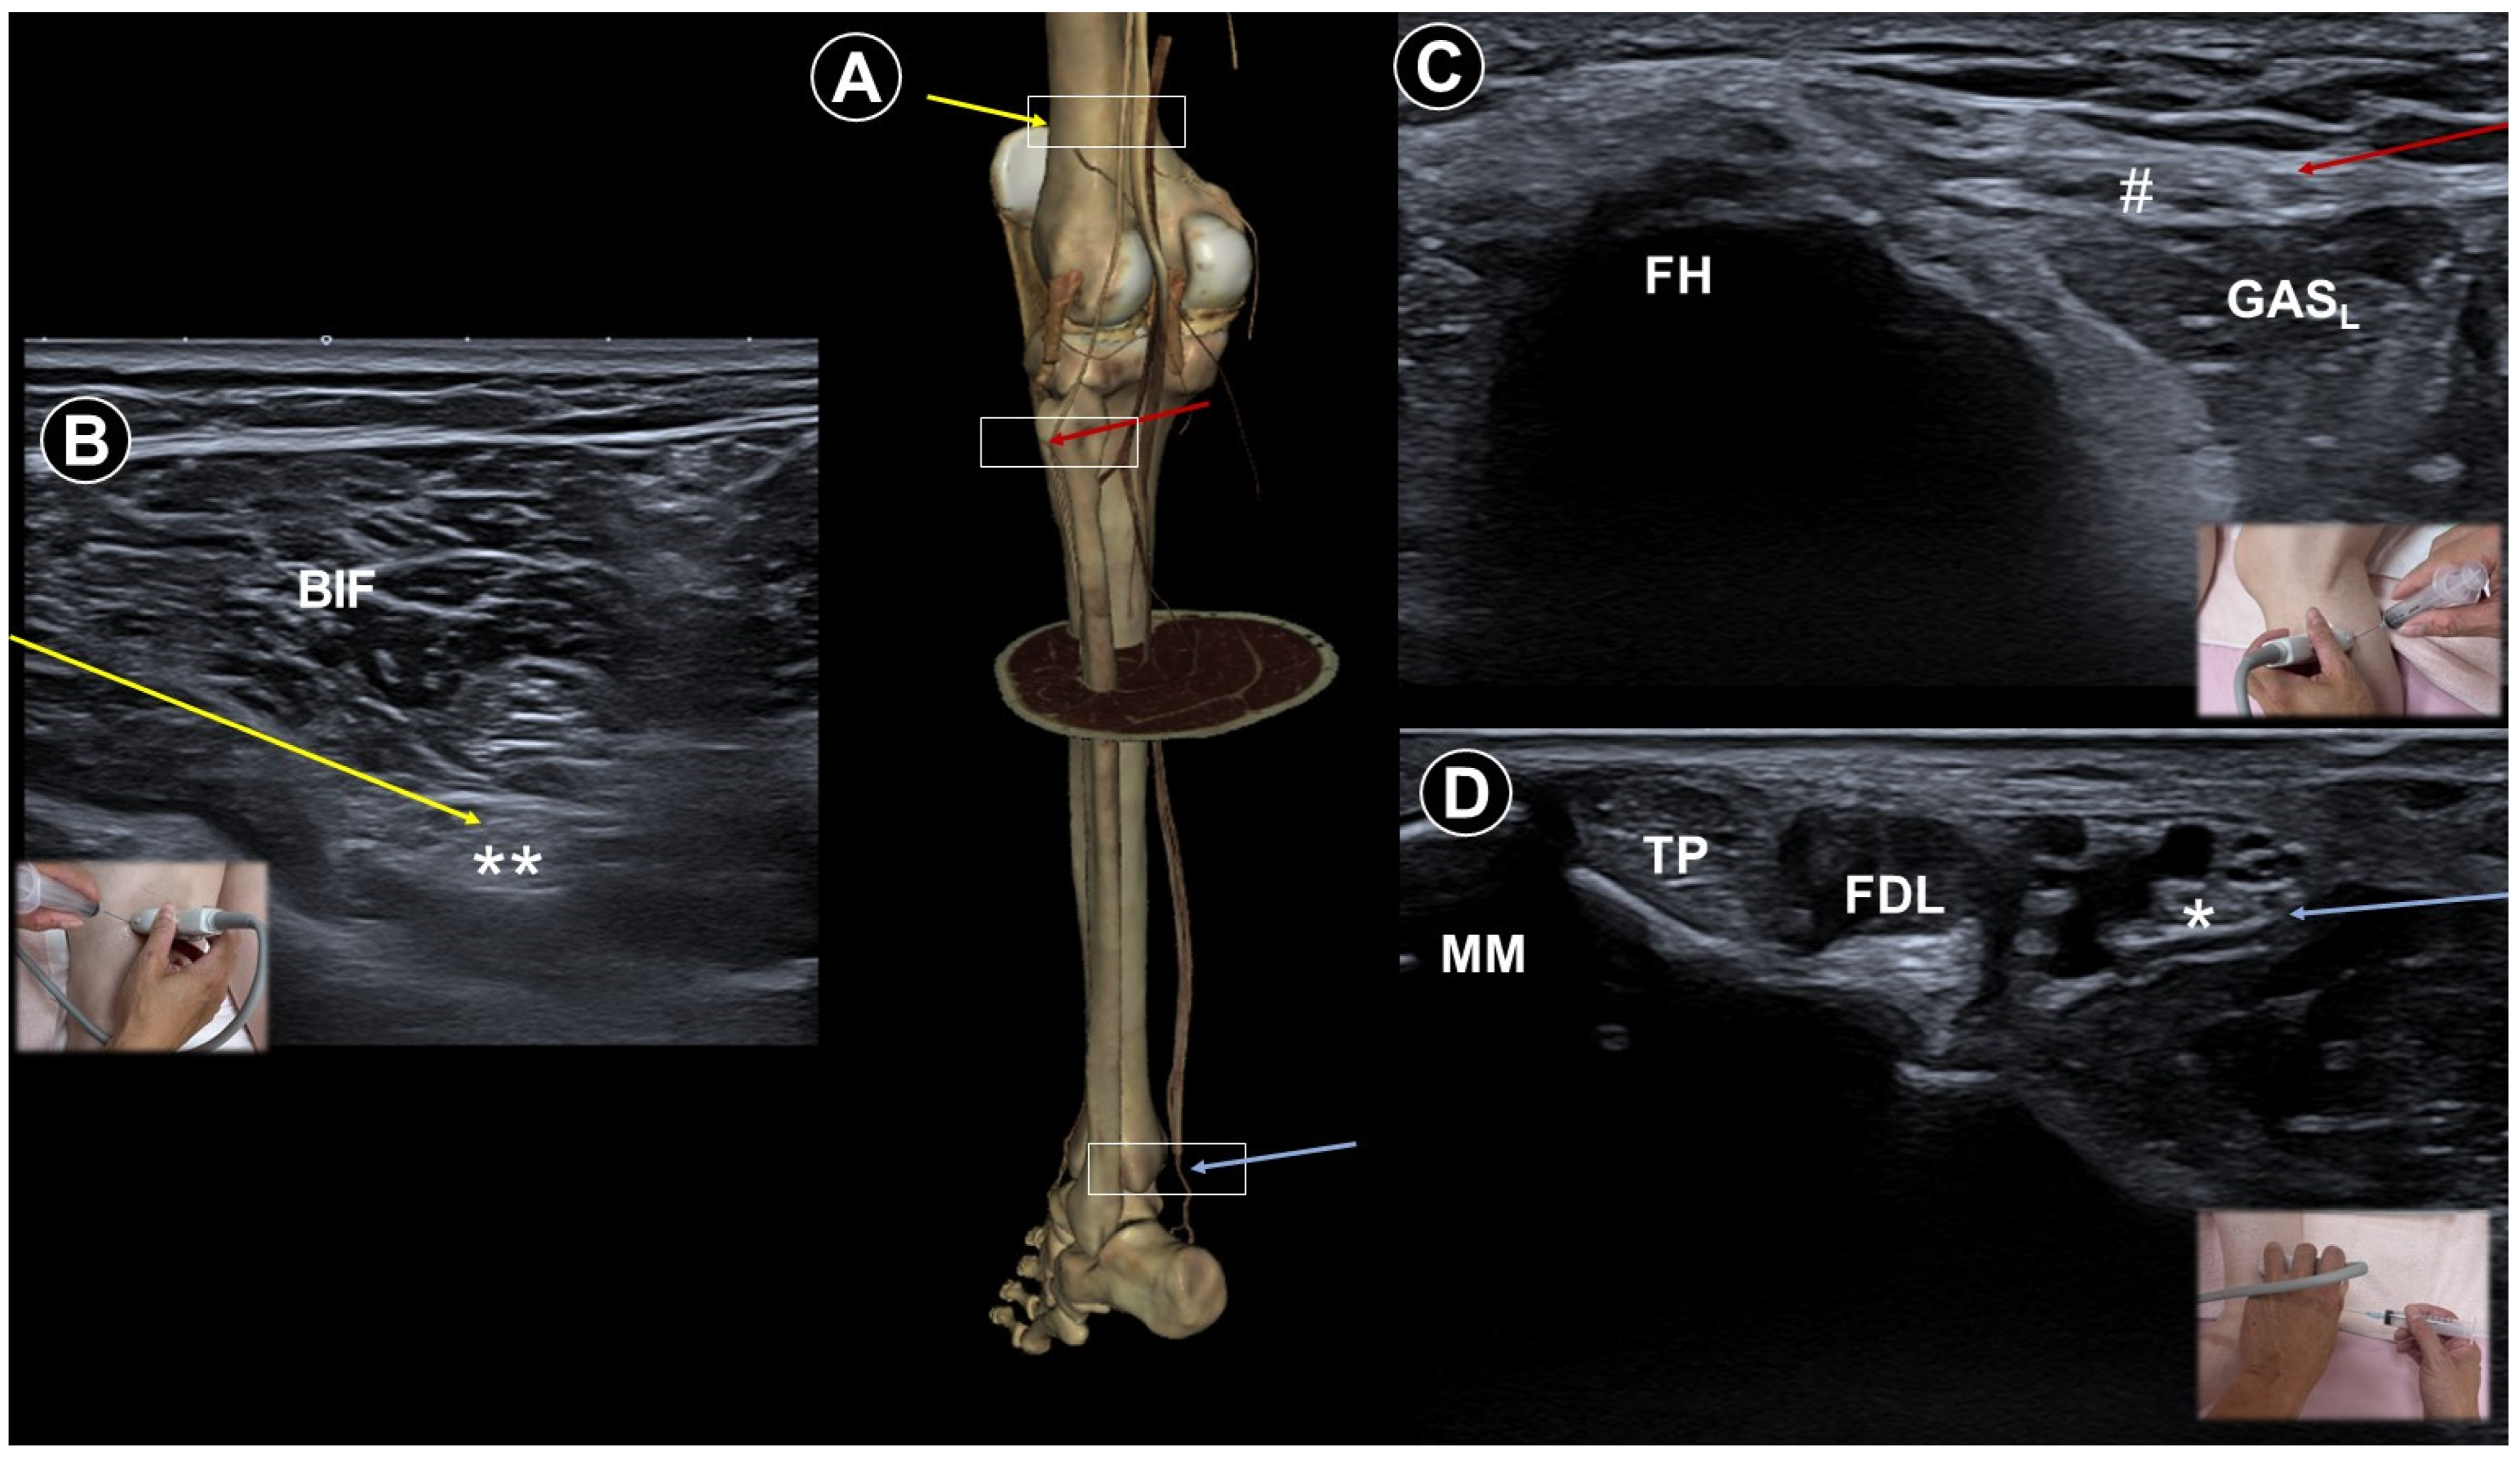

- Hung, C.-Y.; Hsiao, M.-Y.; Özçakar, L.; Chang, K.-V.; Wu, C.-H.; Wang, T.-G.; Chen, W.-S. Sonographic tracking of the lower limb peripheral nerves: A pictorial essay and video demonstration. Am. J. Phys. Med. Rehabil. 2016, 95, 698–708. [Google Scholar] [CrossRef]

- Narouze, S.N.; Zakari, A.; Vydyanathan, A. Ultrasound-guided placement of a permanent percutaneous femoral nerve stimulator leads for the treatment of intractable femoral neuropathy. Pain Physician 2009, 12, E305. [Google Scholar] [CrossRef]

- Lin, C.-P.; Chang, K.-V.; Wu, W.-T.; Özçakar, L. Ultrasound-Guided Peripheral Nerve Stimulation for Knee Pain: A Mini-Review of the Neuroanatomy and the Evidence from Clinical Studies. Pain Med. 2020, 21, S56–S63. [Google Scholar] [CrossRef] [PubMed]